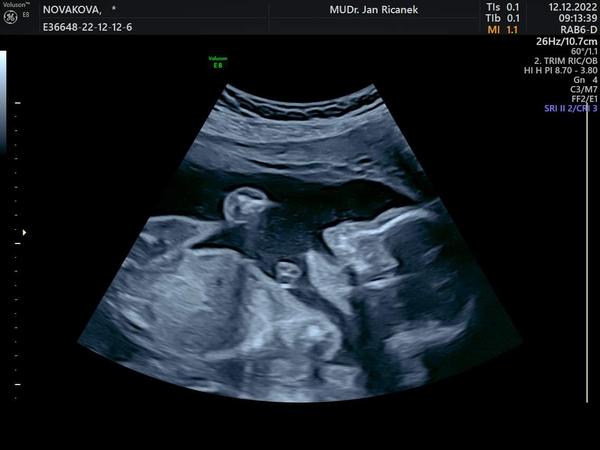

Tak holky dnes 2. trimestralni screening a vse v poradku 🙂 <3

Já mám taky hezkou fotku z poslední kontroly 🤣🤣🤣 má krásnou páteř